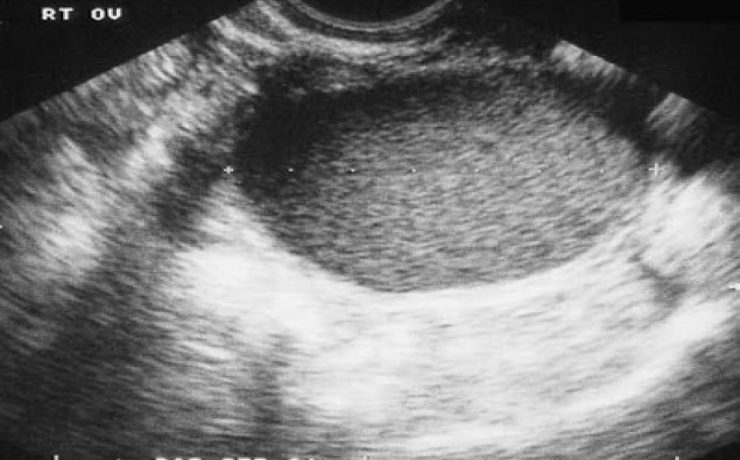

El parénquima esplénico tiene una ecogenicidad similar al hígado y menor que el riñón adyacente. Su valoración ecográfica es útil para confirmar la esplenomegalia y en el estudio de las lesiones esplénicas focales y de los traumatismos abdominales. El aumento del tamaño del bazo, que puede ser difícil de valorar